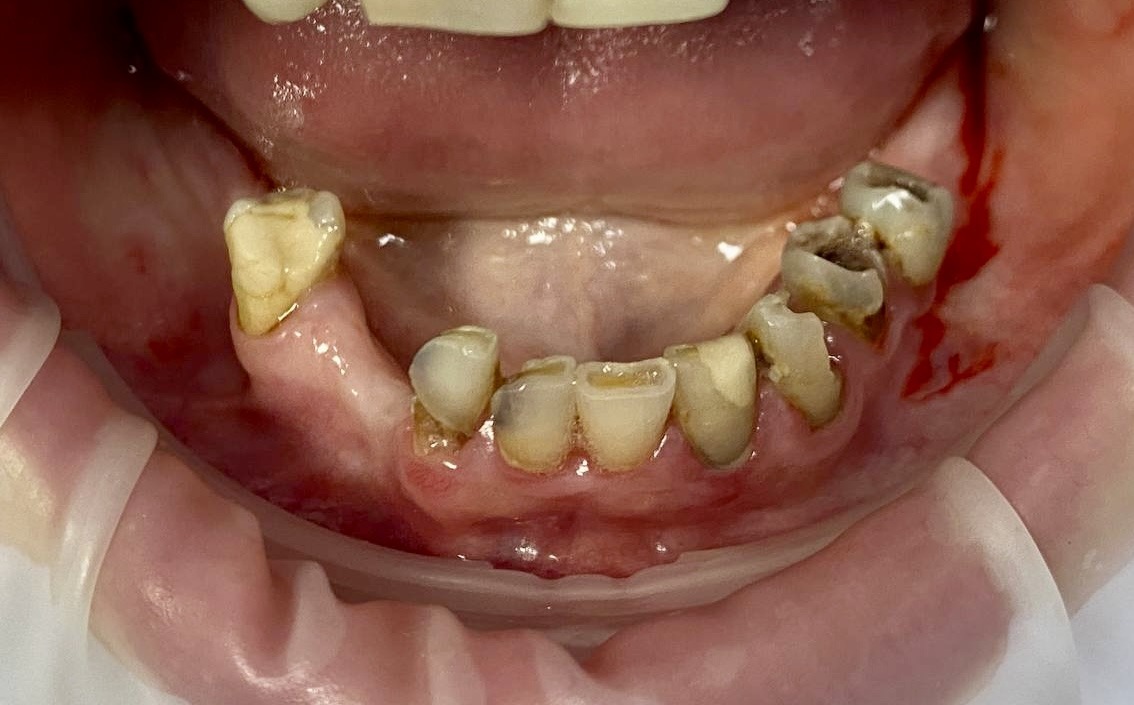

Имплантация по методу all-on-6 на имплантатах Neodent

Пациентка обратилась для имплантации и протезирования нижней челюсти, так как после обследования у терапевта и анализа 3D снимка , были показания к удалению 5 зубов.

После консультации у стоматолога-хирурга была выбрана имплантация по методу all-on-6.

На выбор этого метода повлияла возможность не ожидать 4-6 месяцев приживления имплантатов, а сразу провести протезирование шинирующим акриловым протезом, что было важно для пациентки. В работе использованы имплантаты Neodent. Работа выполнена за 6 дней.